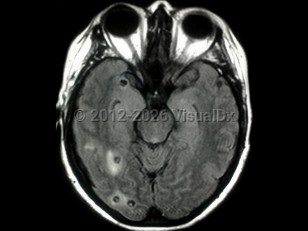

NeurocysticercosisNeurocysticercosis